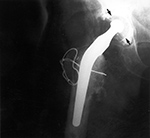

Broken trochanteric osteotomy wire |

A cemented total hip arthroplasty has a trochanteric osteotomy fixed with wires. The wire is broken laterally. The arrows point to evidence of polyethylene wear in the acetabulum. From Benjamin, 1994 |